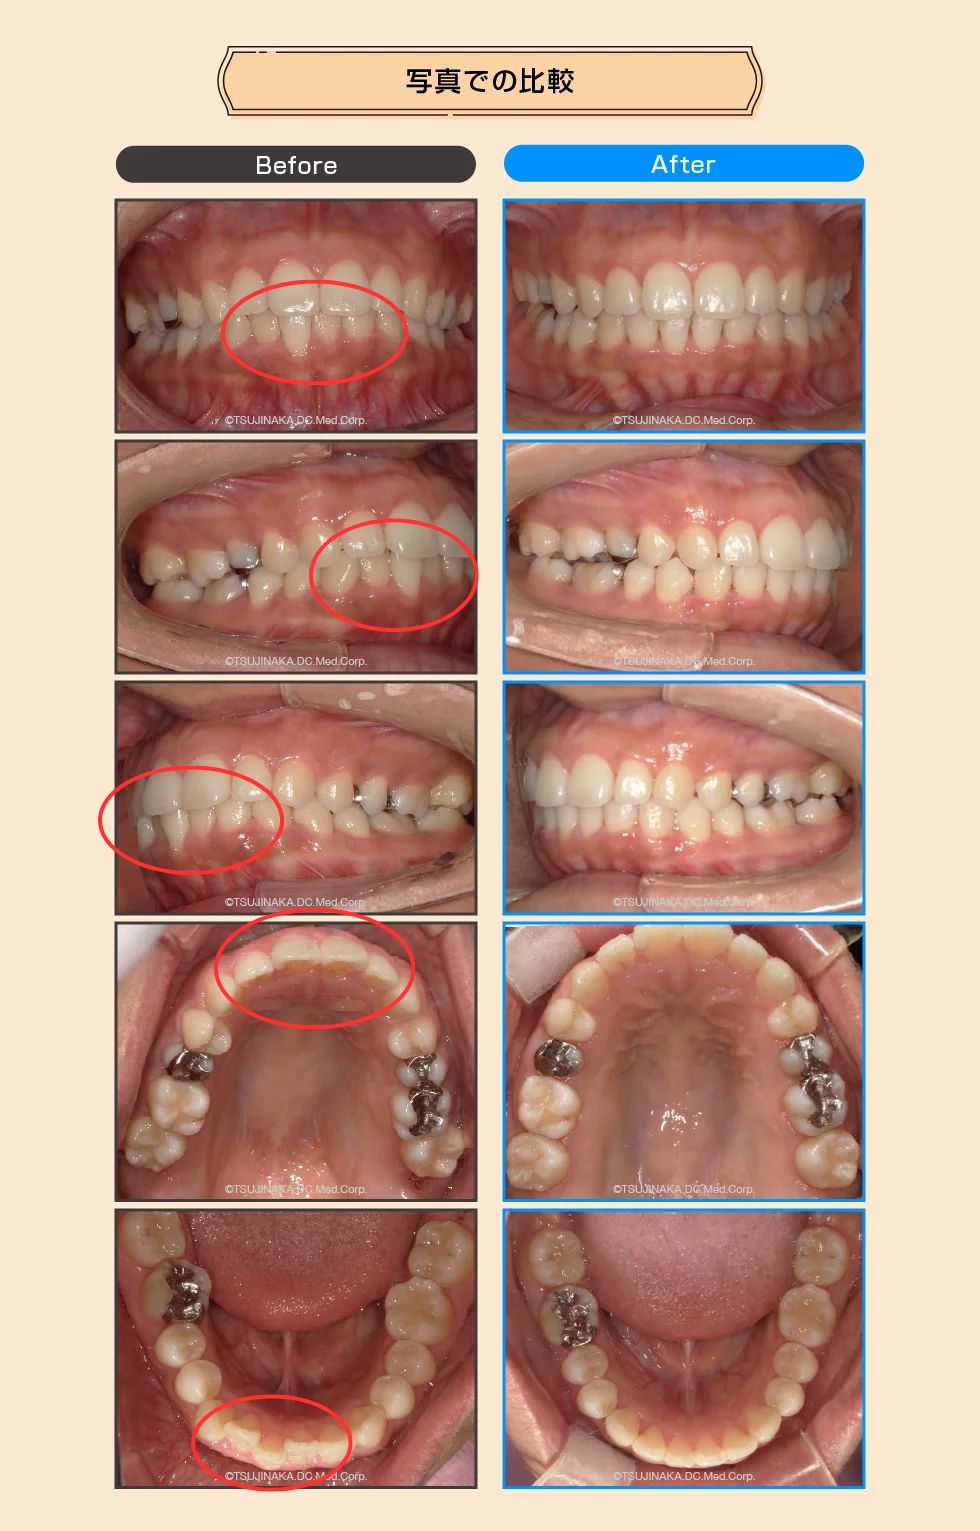

【症例No.6606】数年前から下の前歯が出てきた

数年前から下の前歯が出てきた

この患者さんは反対咬合と叢生歯列だけでは無く、患者さんの気づいてられなかった点として咬合が強く、下顎隆起という噛み合わせが強い人の特徴があった。 治療計画として早期に前歯部の反対咬合を治す必要があった。 反対咬合→叢生歯列→咬合回復 アフターの写真の右下の奥歯(写真左側)を見て貰えると、右下567の3本の歯が真っ直ぐに起き上がって咬み合わせも治っています。

| 主な症状 | 下顎前歯叢生、正中不揃い |

| 治療装置 | マウスピース型矯正装置(インビザライン) |

| 抜歯部位 | なし |

| 治療期間・回数 | 12ヶ月、19回 |

| 治療費概算 | 85万円(税込) |

| リスク・副作用など | 正中を合わせるためにIPRを施した |

| ドクターから一言 | アタッチメントをつける歯が金属だったので仮歯に置き換えてアタッチメントをつけた |